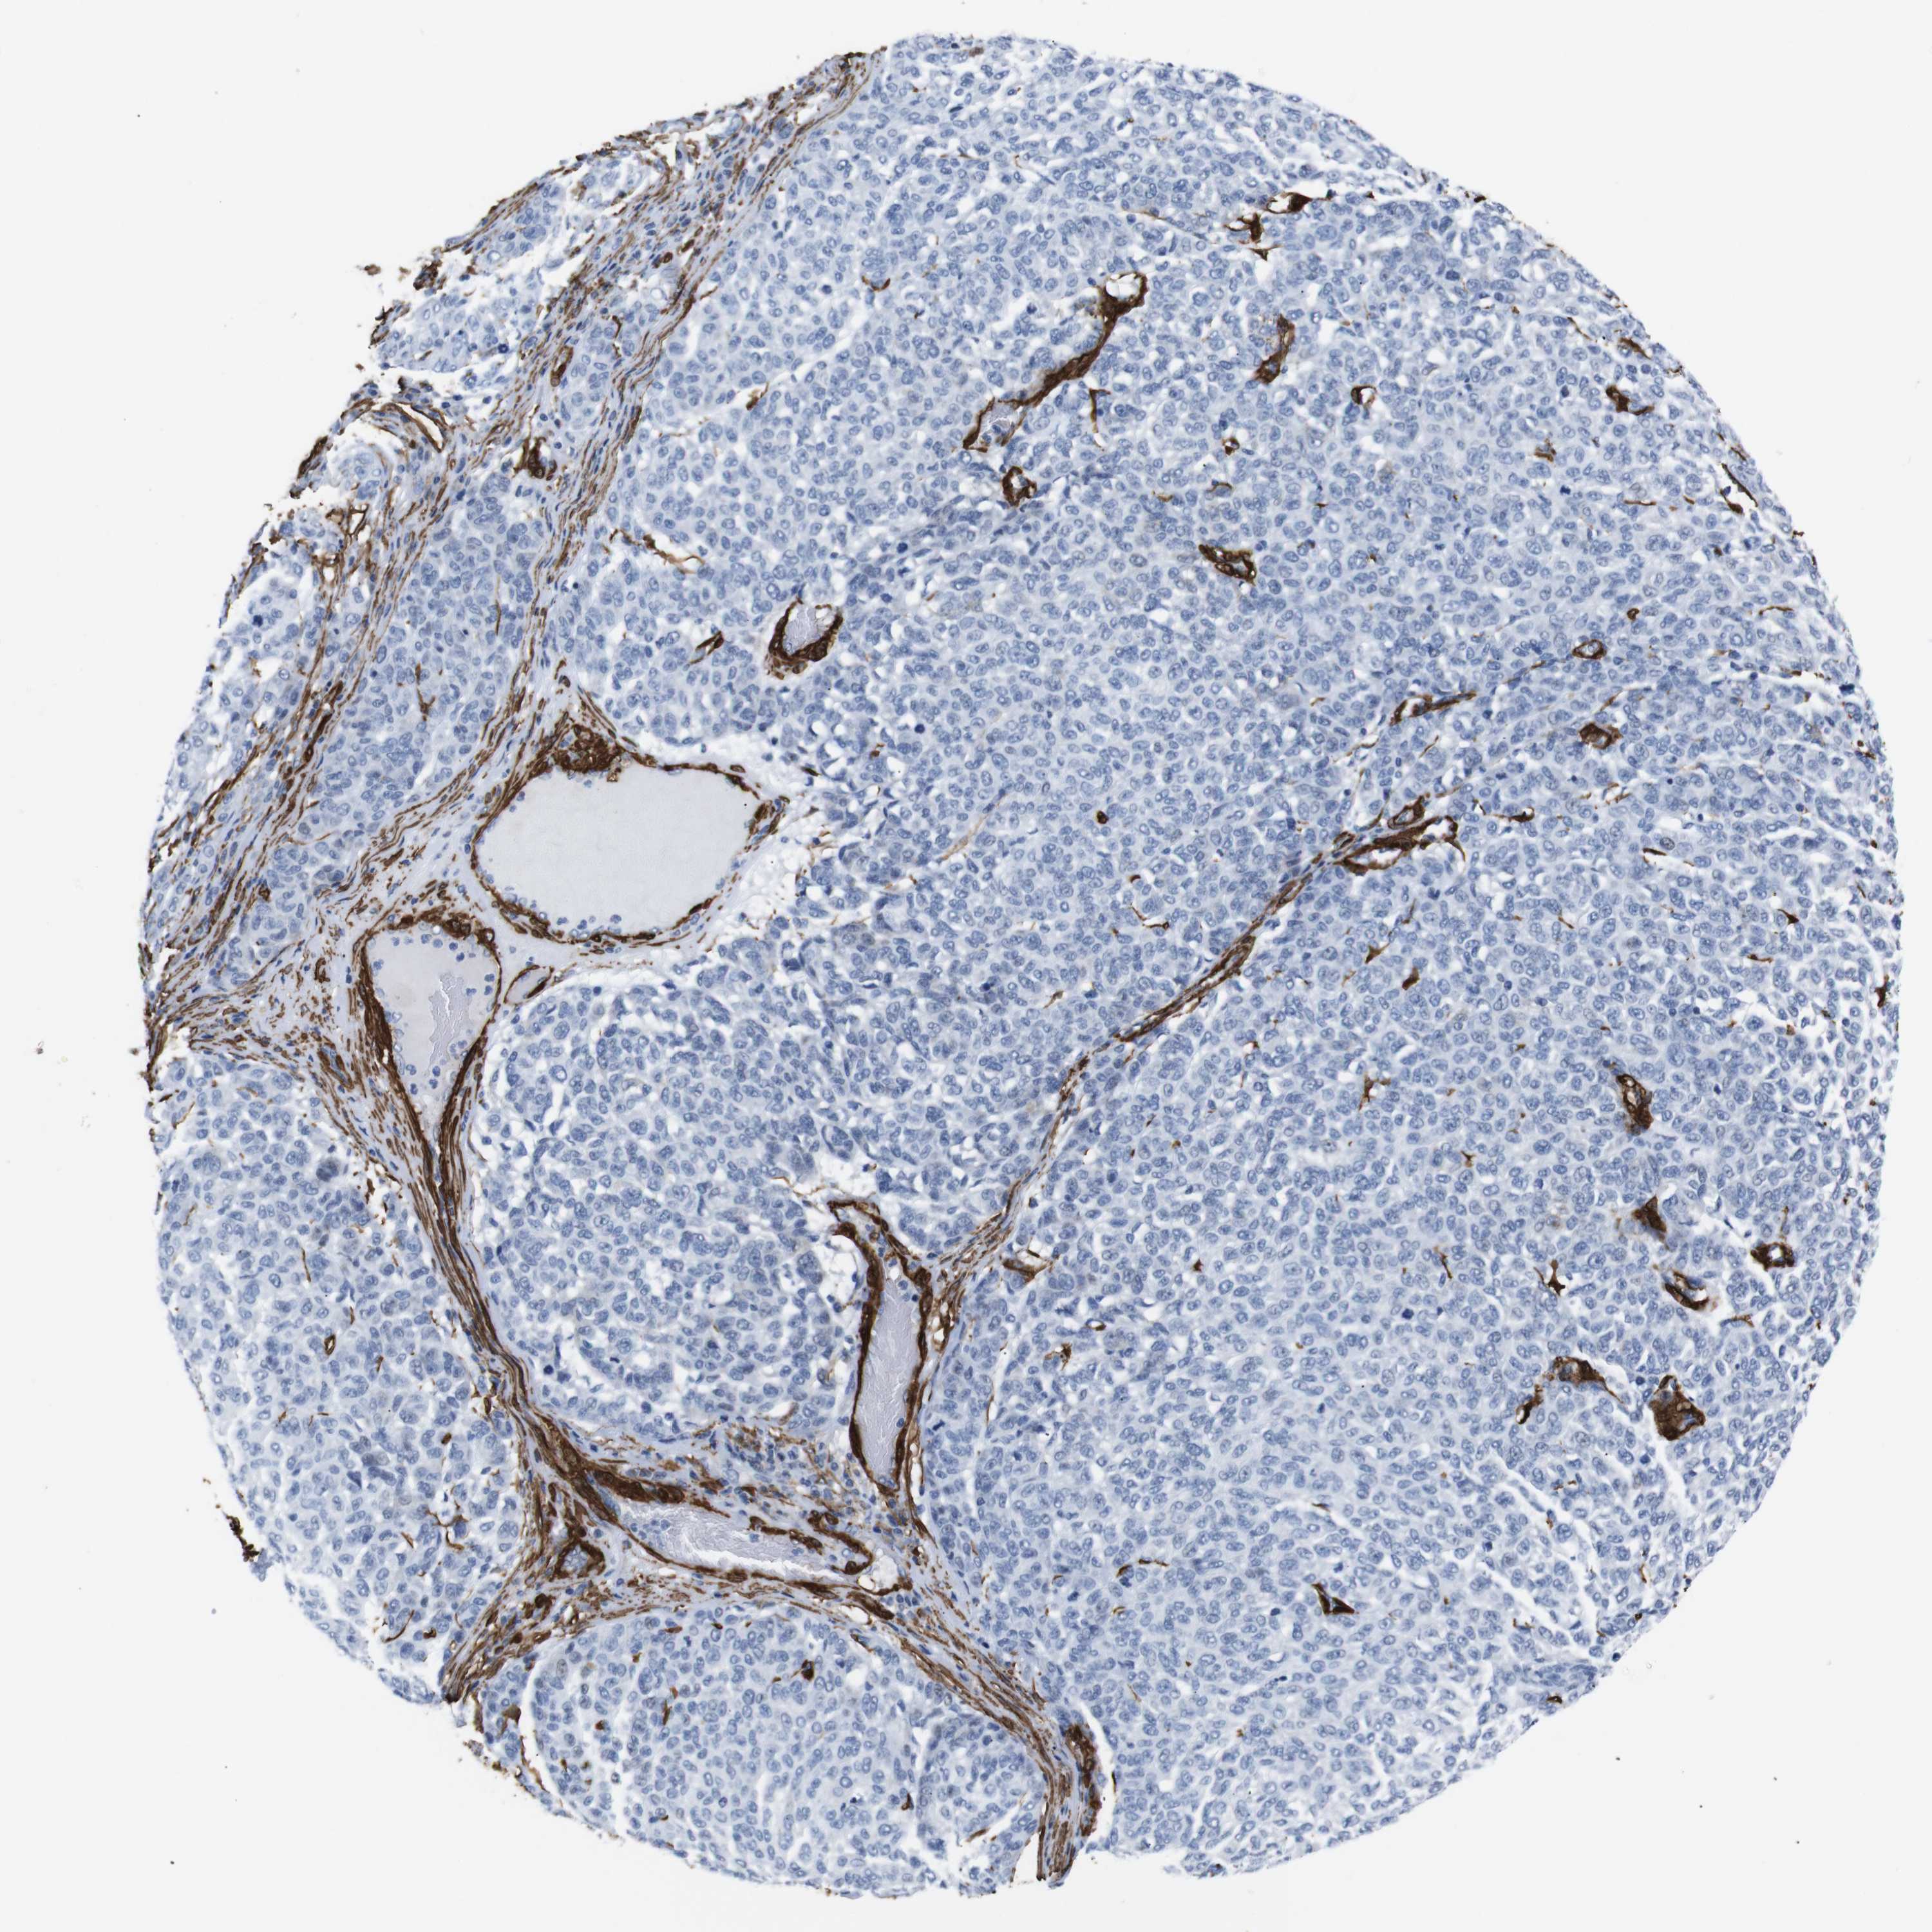

MELANOMA - Protein expressioni

A mouse-over function shows sample information and annotation data. Click on an image to view it in a full screen mode. Samples can be filtered based on level of antibody staining by selecting one or several of the following categories: high, medium, low and not detected. The assay and annotation is described here.

Note that samples used for immunohistochemistry by the Human Protein Atlas do not correspond to samples in the TCGA dataset.

Antibody stainingi

Antibody staining in the annotated cell types in the current human tissue is reported as not detected, low, medium, or high, based on conventional immunohistochemistry profiling in selected tissues. This score is based on the combination of the staining intensity and fraction of stained cells.

Each image is clickable and will lead to virtual microscopy that enables deeper exploration of all samples and also displays staining intensity scores, fraction scores and subcellular localization as well as patient and tissue information for each sample.

HPA041264

HPA041271

CAB000002

CAB003761

CAB013531

Staining

High

Medium

Low

Not detected

Intensity

Strong

Moderate

Weak

Negative

Quantity

>75%

75%-25%

<25%

None

Location

Nuclear

Cytoplasmic/membranous

Cytoplasmic/membranous,nuclear

Malignant melanoma, NOS

Malignant melanoma, Metastatic site